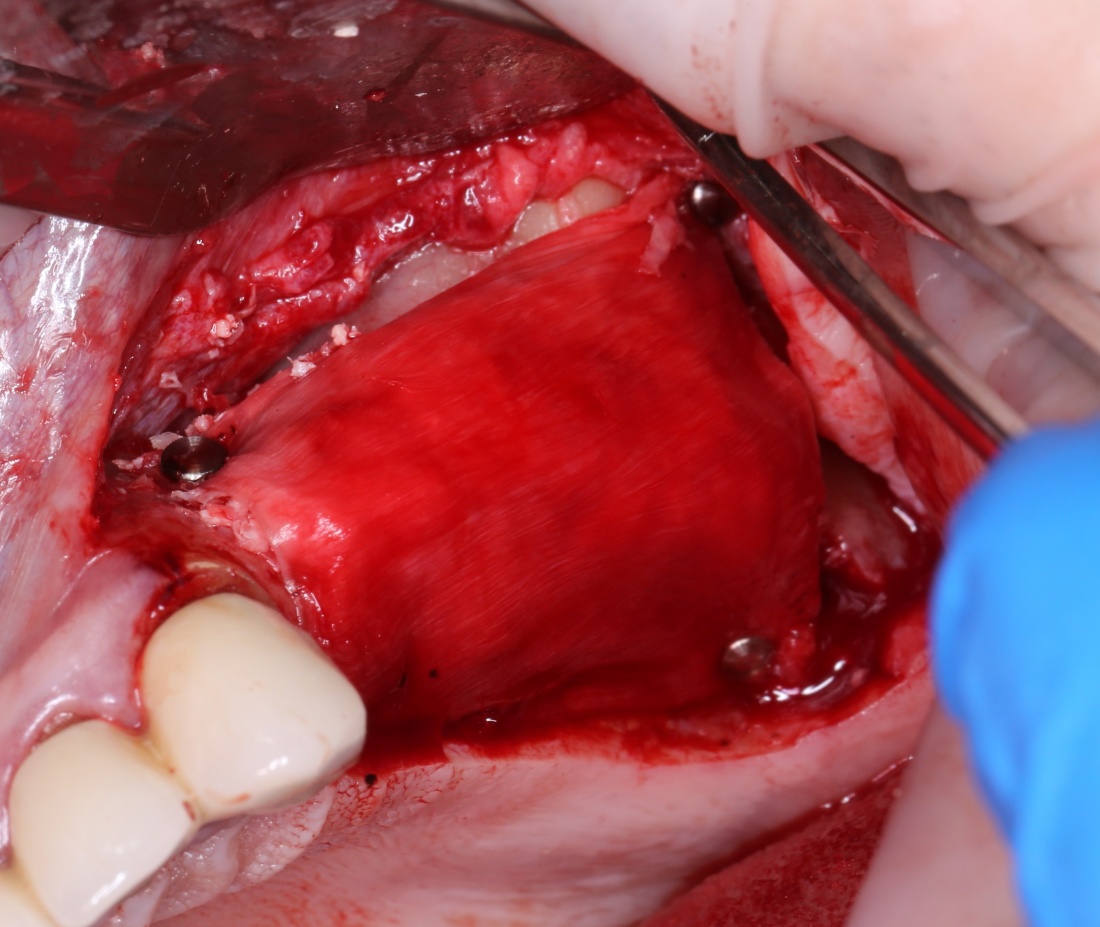

Вариант #3. Использование барьерных мембран

По сути, это «классический» вариант закрытия перфораций шнайдеровой мембраны. Суть проста — мы используем барьерную мембрану типа Bio-Gide или Jason, перекрывая дефект, в среднем, на 30%. Таким образом, мы можем перекрыть даже очень большую перфорацию с достаточно предсказуемым результатом:

Сначала обнаруживаем и выделяем дефект слизистой так, чтобы он максимально уменьшился: